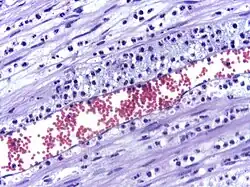

In immunology, leukocyte extravasation (also commonly known as leukocyte adhesion cascade or diapedesis – the passage of cells through the intact vessel wall) is the movement of leukocytes (white blood cells) out of the circulatory system (extravasation) and towards the site of tissue damage or infection. This process forms part of the innate immune response, involving the recruitment of non-specific leukocytes. Monocytes also use this process in the absence of infection or tissue damage during their development into macrophages.

The cytoskeletons of the leukocytes are reorganized in such a way that the leukocytes are spread out over the endothelial cells. In this form, leukocytes extend pseudopodia and pass through gaps between endothelial cells. This passage of cells through the intact vessel wall is called diapedesis.[3] These gaps can form through interactions of the leukocytes with the endothelium, but also autonomously through endothelial mechanics.[4] Transmigration of the leukocyte occurs as PECAM proteins, found on the leukocyte and endothelial cell surfaces, interact and effectively pull the cell through the endothelium. Once through the endothelium, the leukocyte must penetrate the basement membrane. The mechanism for penetration is disputed, but may involve proteolytic digestion of the membrane, mechanical force, or both.[5] The entire process of blood vessel escape is known as diapedesis. Once in the interstitial fluid, leukocytes migrate along a chemotactic gradient towards the site of injury or infection.